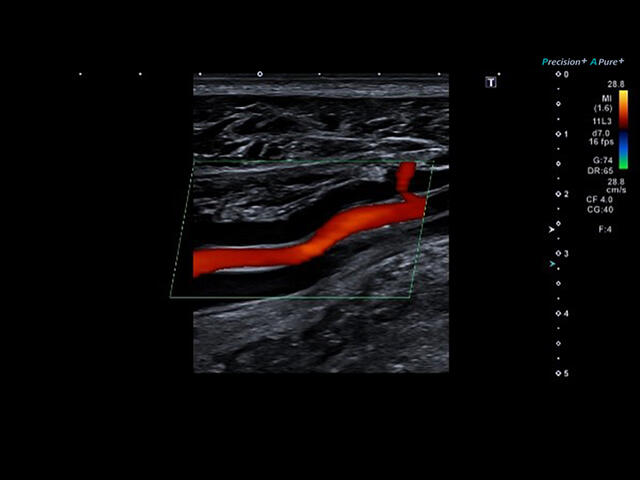

- расширенный динамический поток (ADF),

Aplio a550 может работать с линейным матричным датчиком и поддерживает новейшие монокристаллические датчики. Также Aplio a550 поддерживает большое количество дополнительных опций, таких как - SMI, Компрессионная эластография, Эластография сдвижной волны, Smart Fusion, исследования с использованием контраста (CEUS), 3D реконструкции в реальном времени (4D), функции автоматической оценки подвижности миокарда и фракции выброса.

CDI-Режим - Цветной допплер

DP-Режим - Энергетический доплер

Dir.PD-Режим - Направленный энергетический доплер

Уровень сосудистой визуализации SMI в сочетании с высокой частотой кадров повышает диагностическую достоверность при оценке поражений, кист и опухолей.

SMI с цветовой кодировкой позволяет одновременно отображать информацию о потоках и оттенках серого с высокой временной и пространственной информацией.